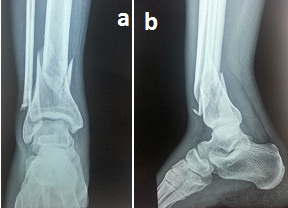

A prospective study was conducted on 18 patients, from October 2012 to September 2014. The ethical clearance was obtained by the ethical committee of our university and consent was obtained from the patients after explaining in detail all the criteria and complications that could occur in the patient’s own language. The inclusion criteria were all skeletally mature patients with fresh intra-articular pilon fractures which satisfied the Ruedi Allgower classification criteria [Table/Fig-1a,b]. Skeletally immature patients and patients with pathological pilon fractures were excluded. Patients with other fractures apart from the pilon fracture which could affect the ankle function were also excluded from the study. A staged surgical protocol was employed for all our patients. The first stage included ankle spanning external fixator application on the day of presentation.

Preoperative anteroposterior and lateral radiographs of the right ankle showing RuediAllgower type II pilon fracture

[Table/Fig-2a&b]. Open fractures underwent wound debridement and external fixator application on the day of presentation. The associated distal fibula fractures underwent open reduction and 1/3rd tubular plate fixation on the day of presentation. Proximal fibula fractures were left alone. A minimum of ten days of waiting period was maintained between the first stage and stage of definitive surgery, wherein antibiotics and anti-oedema measures were instituted.